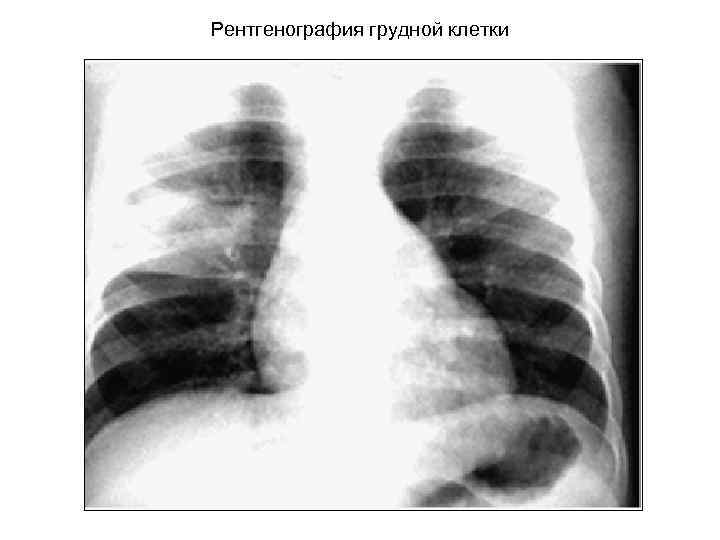

КАРДИТ Критерии кардита: 1. Шумы – впервые выявленные при остром Р или изменение их характера при рецидиве. Систолический шум митральной недостаточности или диастолический шум аортальной недостаточности. Формирование митрального стеноза характерно для ревматической болезни. 2. Ультразвуковые признаки поражения клапанов 3. Увеличение размеров сердца при R – графии 4. Перикардит – шум трения перикарда или признаки выпота при Р-графии или УЗИ. 5. Застойная сердечная недостаточность. Менее достоверные признаки: изменение силы тонов, удлинение P-Q, аритмии и стойкая синусовая тахикардия.

Рентгенография грудной клетки